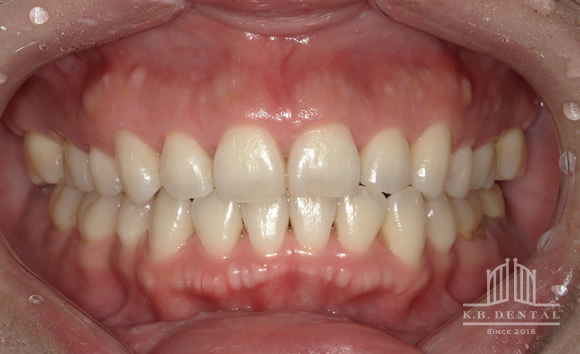

上顎外側骨隆起 症例2(上顎の頬側にできた骨隆起)

笑った時にゴボ口となりやすく、隆起した部分に食物残渣などが生じやすいケースです。静脈麻酔で約1時間半程度要します。

静脈内鎮静法による麻酔代込:約20万円(保険適用外)